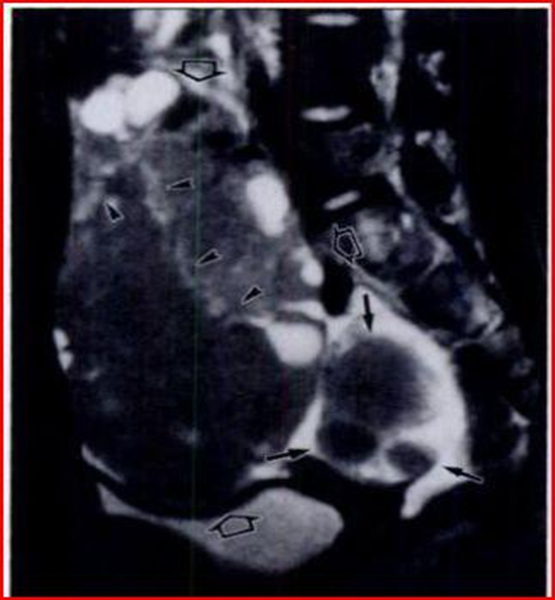

The aim of obtaining a certain diagnosis through the use of imaging techniques, integrated with biopsy and immunohistochemical examination is to avoid unnecessary and extensive surgery in very young patients. Another author who described the figures that appear on imaging in the case of lymphoma with ovarian localization is Mitsumori [6] in fact reports the case of a 12-year-old girl suffering from primary ovarian lymphoma, accurately describing the images provided by the MRI (Figures 11-13).

The T2-weighted image highlights a solid mass with an intermediate signal intensity and a hyperintensity of the septal structures. When gadopentetate dimeglumine is administered intravenously, T1-weighted images reveal marked enlargement of the septa.Numerous small, regular-walled cysts are visible at the periphery of the tumor. In the contralateral ovary, three nonconnected nodules are evident on a T2-weighted image.

These nodules show the same signal intensity as the tumor mass. A needle aspiration biopsy reveals the presence of B-cell non-Hodgking lymphoma. There are three characteristic images in this case:

1) septal structures are hyperintense on T2-weighted images.

2) the periphery of the tumor is delimited by regularly arranged cysts of small size, of uniform volume and with smooth walls (presumably these are ovarian follicles).

3) three independent nodules are present in the contralateral ovary.

The septa that form at the base of the interstitial structures of the ovary, in step with tumor growth, appear hypointense on T2-weighted images, given that they contain fibrous tissue. In this case, however, the septae most likely appear hypointense due to a decrease in fibrous tissue and the presence of edema. The cortical structure of the ovary appears well preserved after surgical resection carried out following chemotherapy. At the basis of these pathological figures Mitsumori believes that the small regularly shaped cysts observed peripherally are the ovarian follicles of the cortex.

In the process of tumor growth, in fact, the lymphoma tends to invade the ovary, preserving its normal structure. In fact, as we will see later, cystic areas are characteristic of other types of ovarian tumors, such as metastases from a colorectal neoplasm. Mitsumori then underlines how the cysts found represent ovarian follicles. It is extremely rare to see more than one solid tumor in the same ovary on MRI.

Figure 11: Sagittal T2-weighted MRI image shows that the tumor has intermediate signal intensity (open arrows) and there are hyperintense septal structures within the tumor (arrowheads). In the contralateral ovary there are three disconnected nodules (black arrows).

Figure 12: Sagittal T1-weighted MRI image, septa show increased signal intensity after administration of gadopentetate dimeglumine (arrowheads).

Figure 13: Axial T1-weighted MRI images with gadopentetate dimeglumine administration show many small, uniformly sized, smooth-walled cysts at the periphery of the mass (arrowheads).